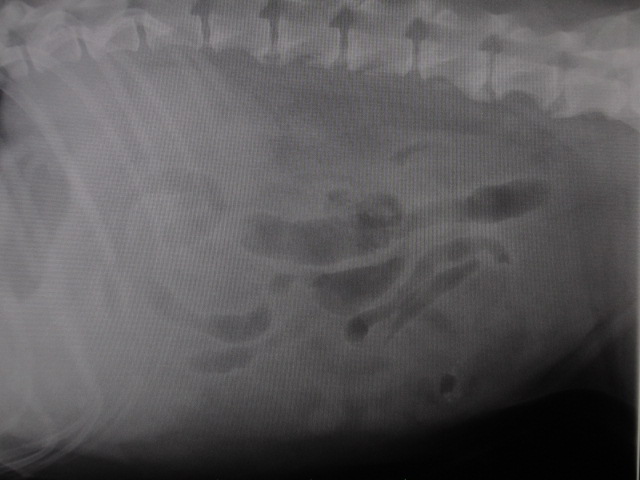

術前のレントゲンです。

脂肪も多く、腫瘍の位置がよくわかりません。